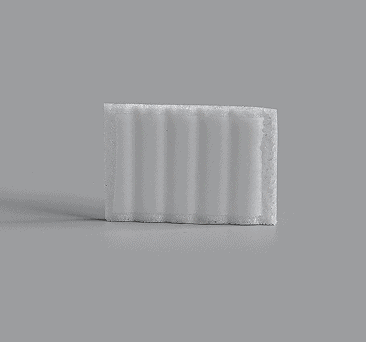

Block